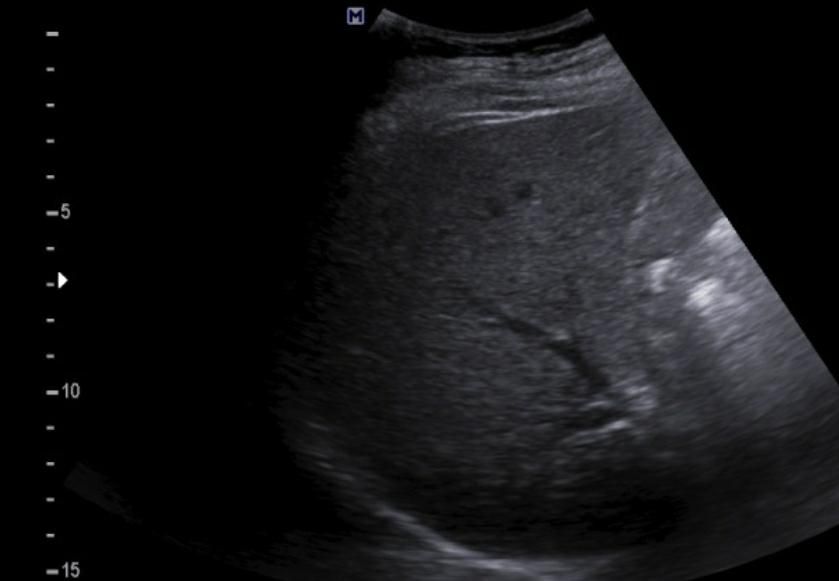

간에 혹이 있는건가요? 초음파 사진 봐주세요

간에 혹이 있는건지 맞다면 크기나 모양이 혈종인지 아이면 암으로 의심이 되는지 초음파 사진 봐주세요...ㅜㅜㅜ꼭 답변 부탁드립니다

• 3번 째 사진

간 초음파로만 봐서는 약간의 지방간이 관찰되지만 혈종으로 의심되지는

않으며 사진 우측에 보이는 동그란 부분은 장의 단면이 관찰되었을 가능성이

높은 것으로 보입니다